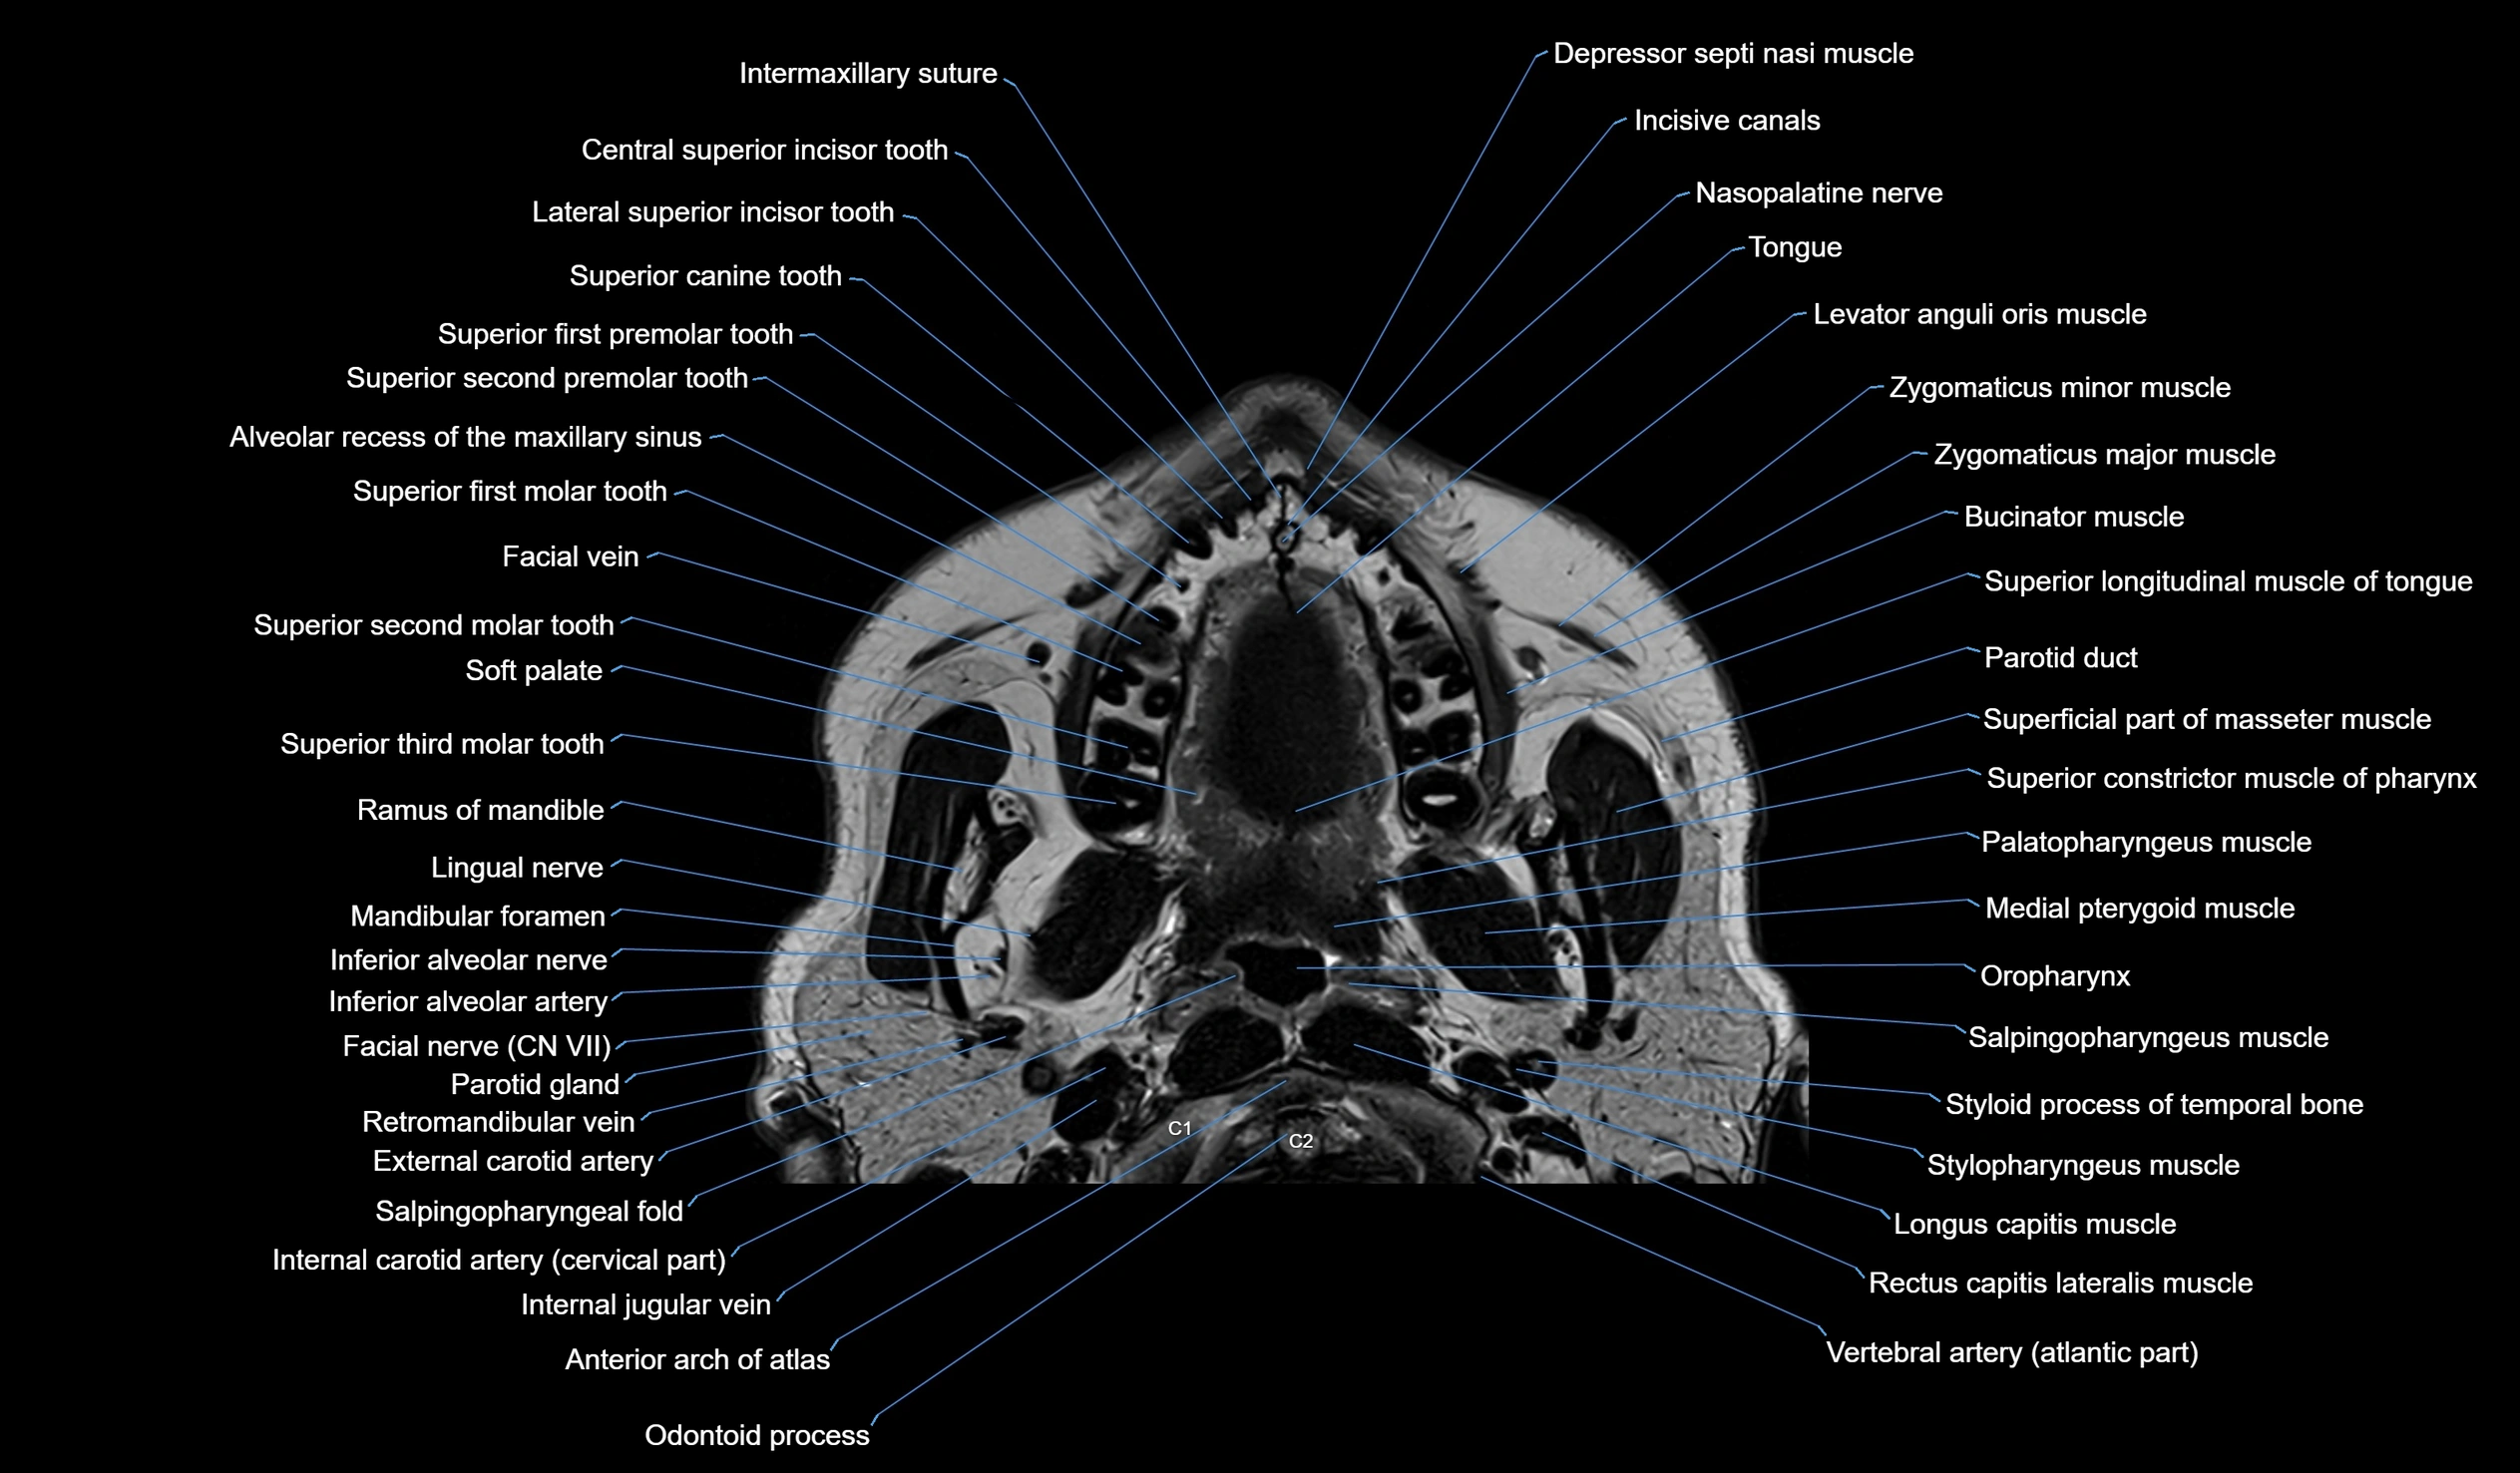

MRI images